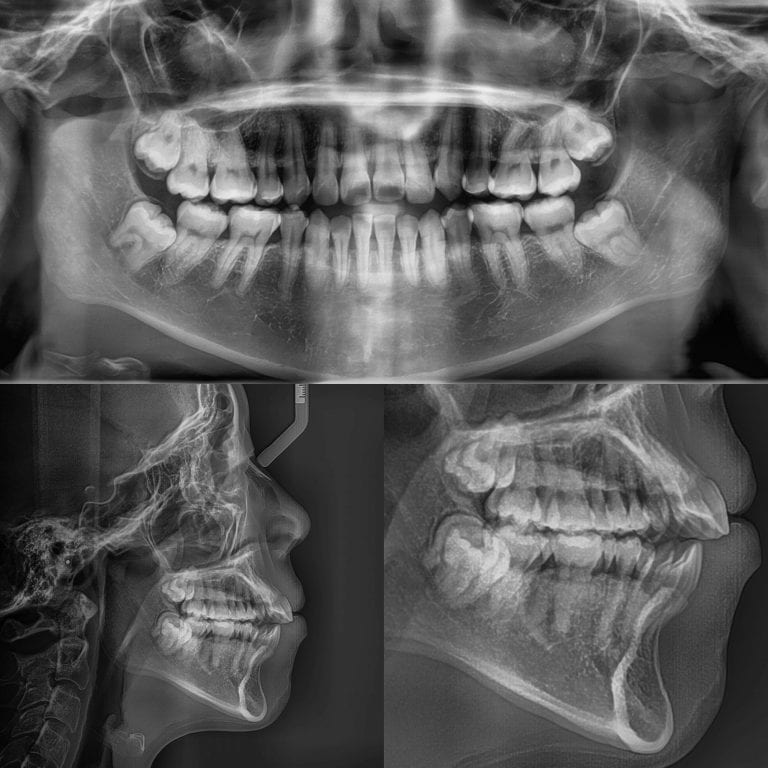

In our office, we use digital radiography which allows us to take x-rays using 90% less radiation than conventional x-rays. This digital technique also allows us to enhance the images for better diagnosis of any dental concerns.

- Merrell & Nichols Dentistry, we understand how crucial it is to get accurate and real-time diagnostics for my patients. Gone are the days when traditional x-rays are the only option for observing and diagnosing oral and dental issues. Digital x-rays are now the norm in most dental practices, including our very own Merrell & Nichols Dentistry. Not only are they safer and more efficient, but they also provide a better patient experience. With digital x-rays, we can look for changes in the teeth and jawbone, cavities, and any signs of infection or inflammation. In particular, digital x-rays allow us to spot problems that can't be seen with the naked eye, such as impacted teeth or cysts. Digital X-rays also provide us with a detailed overview of your oral health, allowing us to detect any areas of concern quickly and accurately.

Traditional X-rays are used to emit radiation that can pose health risks if delivered in high doses. Our digital X-rays use 90% less radiation than conventional x-rays. One of the most critical benefits of digital X-rays is the minimum radiation exposure they provide.

Gone are the days when patients have to wait a couple of days to get X-ray results. With digital X-rays, they are readily available almost instantly as the images are sent directly to a computer for review. Digital X-rays can also be zoomed in or enhanced, making it easier to see and diagnose potential dental issues.

Digital X-rays provide superior diagnostic capabilities compared to traditional X-rays. The high-resolution images offer more detailed information on the teeth, jaw, and surrounding tissues. As a result, dentists can identify dental issues earlier and determine the best course of action for effective treatment.